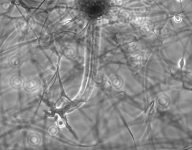

| Species Name: | Rhizopus microsporus var. microsporus |

| Taxonomy: | FUNGI Mucoromycota, Mucoromycetes, Mucorales, Rhizopodaceae |

| Substrate: | sputum, male 61 yr with chronic obstructive pulmonary disease and untreated diabetes | Location: | USA Massachusetts, Worcester (GEO: 42.263,-71.802) |

| Characters: | HUMAN/ ANIMAL PATHOGEN multifocal lung infection following brush clearing - Tsyrkunou AV, Ellison RT 3rd, Akalin A, Wiederhold N, Sutton DA, Lindner J, Fan H, Levitz SM, Zivna I, Med Mycol Case Rep. 8;6:14-7, 2014 (Click for publications citing UAMH 11833) |